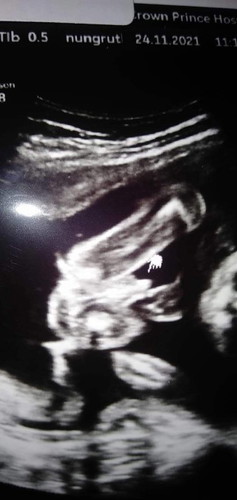

เพศลูก ในภาพเป็นหญิงหรือชายค่ะ

แบบนี้ผู้ชายหรือผู้หญิงค่ะเเม่ดูไม่เป็น ช่วยบอกหน่อยค่ะ 😁😊 (ในใจอยากได้ผู้ชายมากค่ะ)#ขอบคุณสำหรับคำตอบค่ะ #ท้องแรกคะ #ขอบคุณล่วงหน้านะคะ

บ้านนี้คุณพ่ออยากได้ผู้หญิง โด่มาขนาดนี้คงไม่ต้องลุ้นให้เป็นหญิงล่ะ5555 ซาวด์ตอน28วีคจ้า

ชายจ้า ปิก้าจู โผล่แล้วจ้า

เหมือนกระจู๋เลยแม่ 🤣🤣